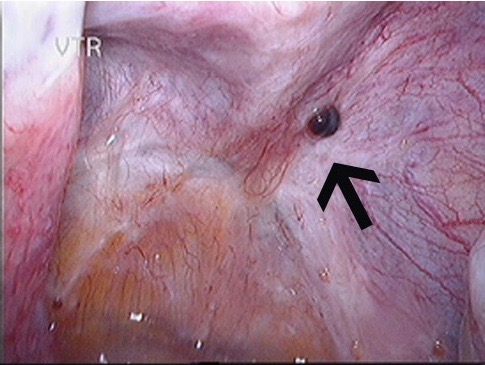

The image on the left shows a normal pelvis while the one on the right shows superficial endometriosis deposits.

In the majority of women with endometriosis, the endometriosis found in the pelvis has only implanted superficially. Superficial lesions of endometriosis can never be diagnosed on ultrasound as they have no real mass, only colour, which cannot be detected with ultrasound. These lesions can cause as much pain as some deep infiltrating lesions but they can only be seen on laparoscopy. They may be removed during a laparoscopy and special preoperative measures are rarely required.